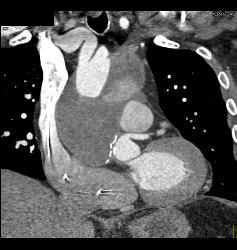

Dissection in Abdominal Aorta